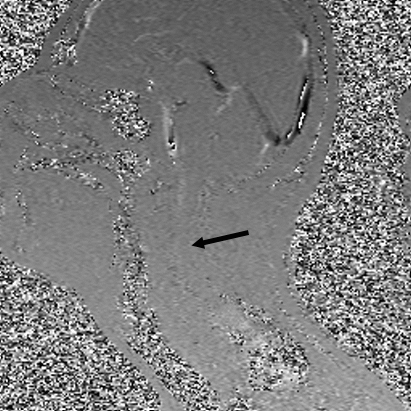

Тем не менее в последнее десятилетие в МРТ произошел своего рода ренессанс, который впервые позволяет нам наблюдать за движением спинномозговой жидкости. Анимированное GIF-изображение ниже (исследование движения спинномозговой жидкости) — одно из тех изображений, которые используют очень продвинутую физику, чтобы показать, как спинномозговая жидкость (пульсирующая темная материя) течет по спинному мозгу, и, фактически, в этом случае она немного заблокирована примерно на уровне C5 (стрелка).